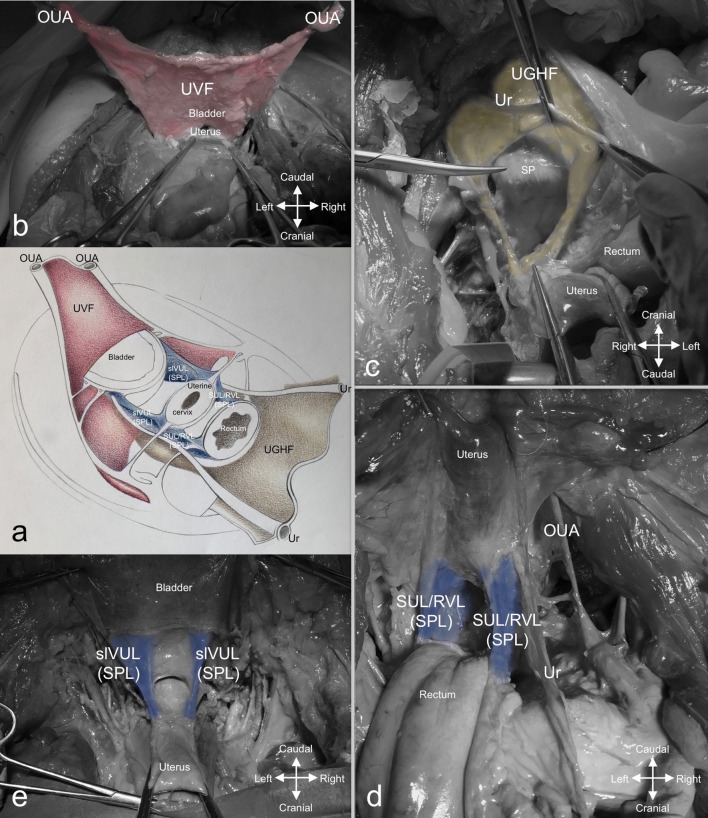

Fig. 2.

Deep fascial-ligamentous retroperitoneal structures responsible for the creation of compartments. a Schematic illustration of the deep fascial-ligamentous retroperitoneal structures: the UVF, the UGHF, the SPL. b The UVF. c The UGHF. d The SUL/RVL complex. e The slVUL. OUA obliterated umbilical artery, slVUL superficial layer of the vesicouterine ligament, SPL sacropubic ligament, SUL/RVL sacrouterine/rectovaginal ligament complex, UGHF urogenital-hypogastric fascia, Ur ureter, UVF umbilicovesical fascia

The UGHF (Fig. 2a, c) is the inferomedial extension of the double sheath renal fascia, enveloping the superior hypogastric plexus (SHP) on the sacral promontory, the ureters and the gonadal vessels; downwards, it accompanies the ureters to the bladder and the hypogastric nerves (HNs) to join the inferior hypogastric plexus (IHP) in a sort of mesentery-like structure called mesoureter (Yang et al. 2014; Coffin et al. 2015): the ventral sheath separates the hypogastric nerves from the mesorectum, whereas the dorsal one extends along the ventral aspect of the great vessels and the psoas major muscle (Diarra et al. 1997). As there is no internationally accepted standard nomenclature for this fascia, it can be found described in literature by several terms, i.e., presacral fascia, endopelvic fascia, urogenital fascia and pre-hypogastric nerve fascia (Ercoli et al. 2005; Havenga et al. 1996; Ceccaroni et al. 2006; Kinugasa et al. 2008).

The SPL (Fig. 2a, d, e), which extends from the sacral foramina to the pubis on the sides of the pelvic organs, is the fascial-ligamentous bundle that originates from the visceral reflection of the pelvic parietal fascia (Ercoli et al. 2011). The SPL is called: the SUL between the sacrum and uterus, the rectovaginal ligament (RVL) between the rectum and vagina (Fig. 2d); the superficial layer of the vesicouterine ligament (slVUL) between the vagina and bladder (Fig. 2e); the pubovesical ligament between the bladder and pubis (Ramanah et al. 2012).

The SPL was easily detected in its portion that extended between the rectum and the bladder. Indeed, the thickness of the SUL/RVL complex (Fig. 2d) and the slVUL (Fig. 2e) made them raise the peritoneum, creating two folds which became visible landmarks during the dissection in all cadavers. Conversely, the portions of the SPL dorsal to the rectum and ventral to the bladder were not so relevant for surgical purposes except for one cadaver where the pubovesical ligaments were clearly visible.